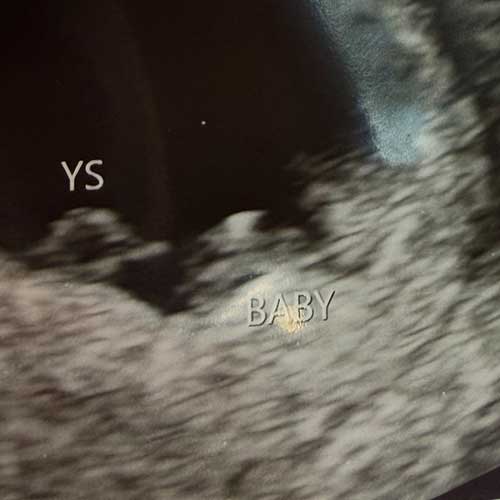

Will Oren get a brother or sister?